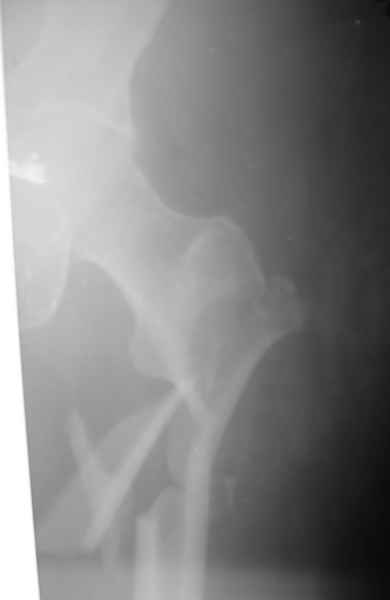

К сожалению никакой информации кроме рентгенограммы

одного из бедер, и то в одной проекции не представлено. Но и исходя из представленного снимка я бы предпочёл длинную гамму(производитель в принципе значения не имеет, если это не подпольная организация).

По представленному снимку выполнял бы антеградное введение стержня, длинна дистального отломка позволяет. Только блокирование более чем в одной плоскости.

Современная генерация бедренных гвоздей ChM позволяет "перекрыть" все бедро. Почему "правый гвоздь на левое бедро"?

Я бы поставил слева любой проксимальный гвоздь. Подойдет и стандартный СhM в "реконструктивном" варианте. А справа - хоть антеградно, хоть ретроградно - кому что нравится. Я бы колено сверлить не стал. Ввел бы в дистальный отломок 3-4 винта обязательно в 2-х плоскостях.